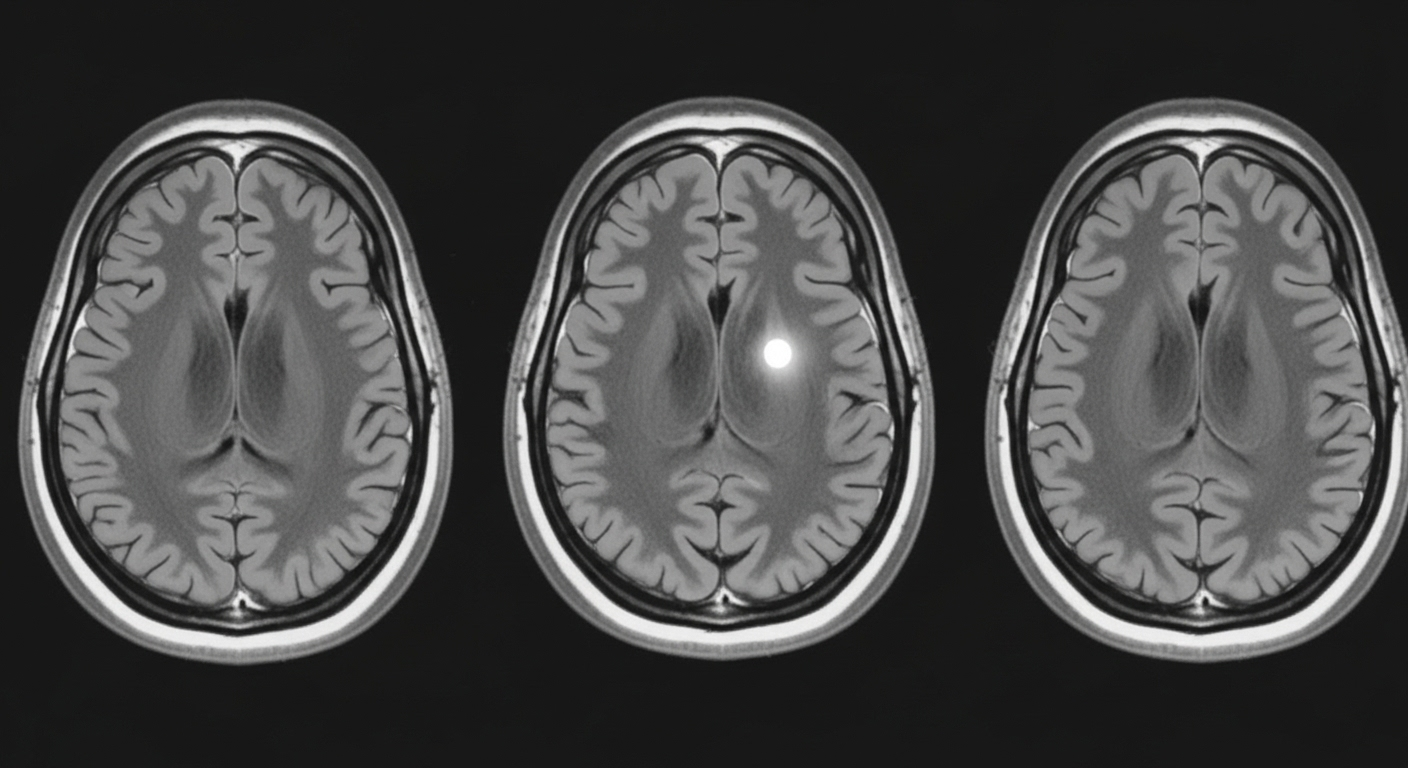

Dans de très rares situations, notamment chez certaines personnes souffrant d’épilepsie du lobe temporal, le déjà-vu peut être un signe avant-coureur d’une crise. Mais là encore, il s’inscrit dans un tableau clinique bien plus large et ne constitue jamais un symptôme isolé.